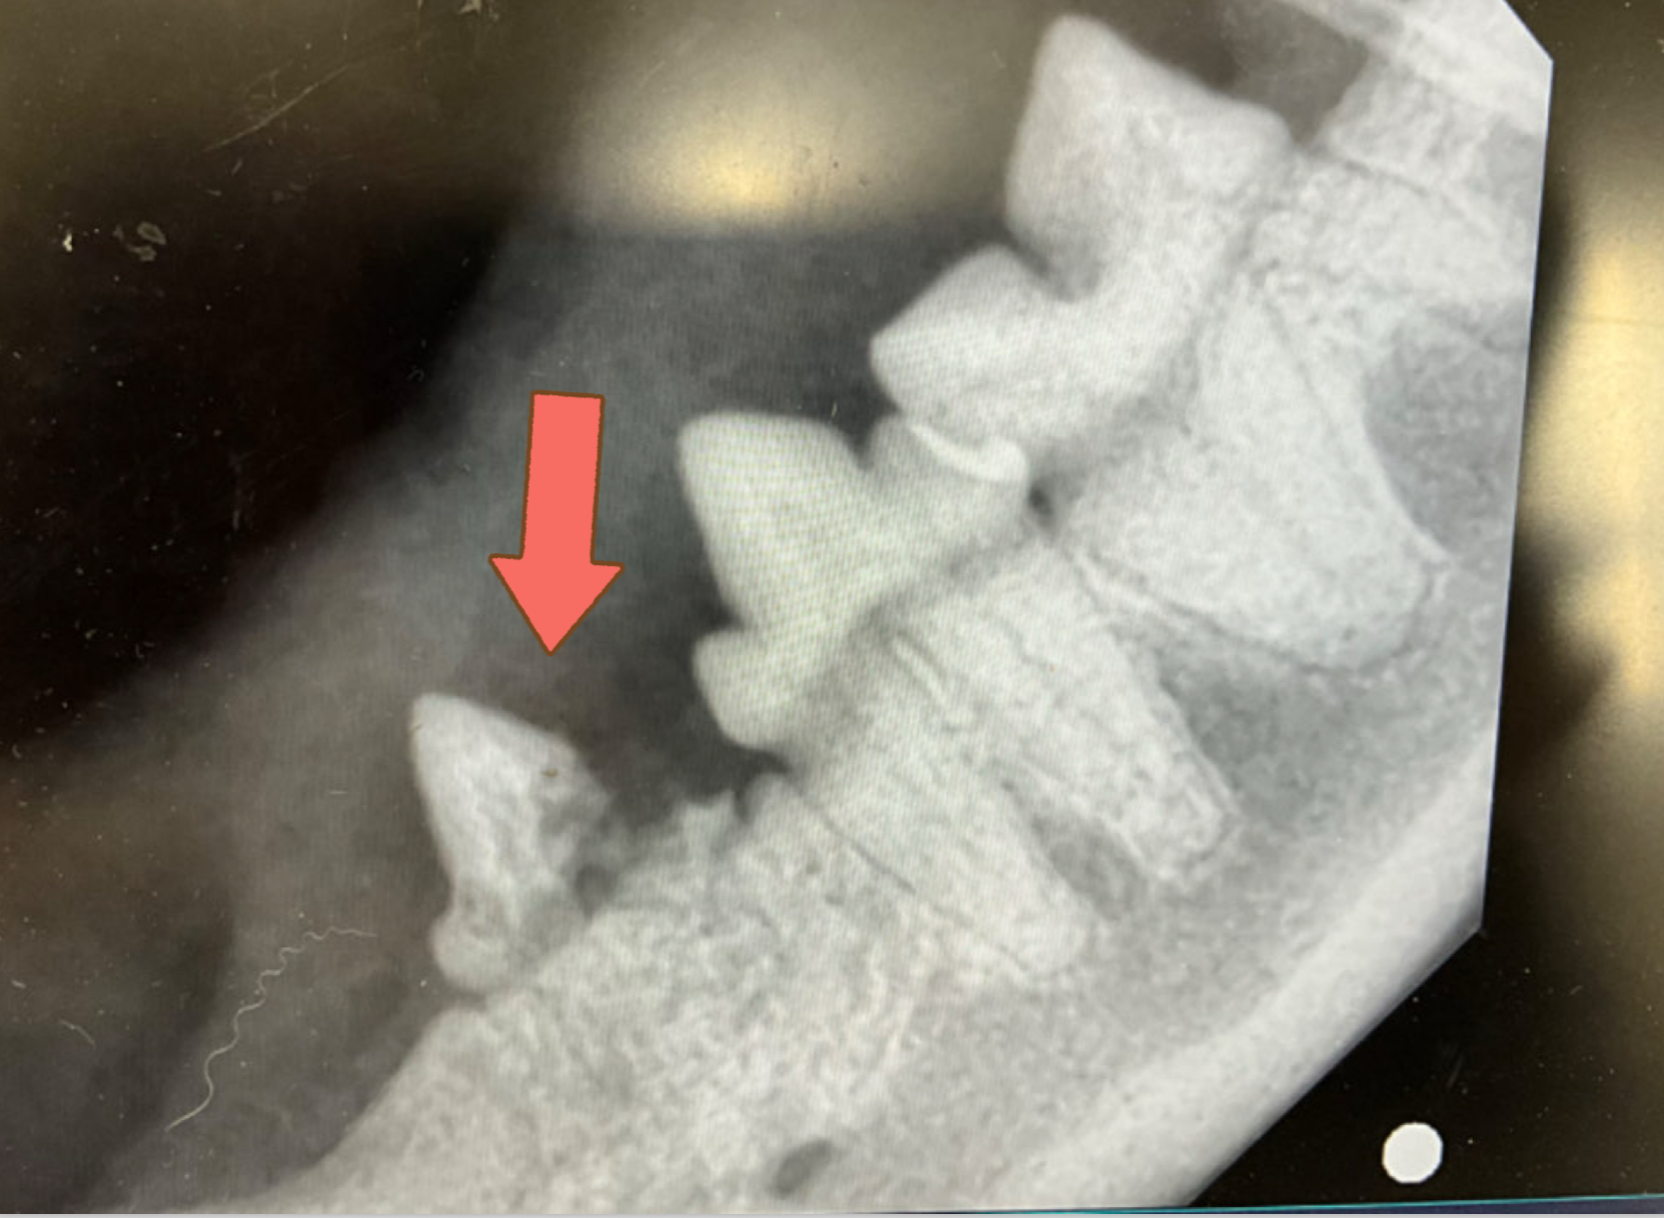

身体検査では、吸収病巣の好発部位でもある左右下顎の第2前臼歯で病変を認めました。

全身麻酔下で歯のレントゲンを撮影すると歯の付け根あたりから歯が溶けたように吸収されて一部骨に置き換わっているのが分かります。